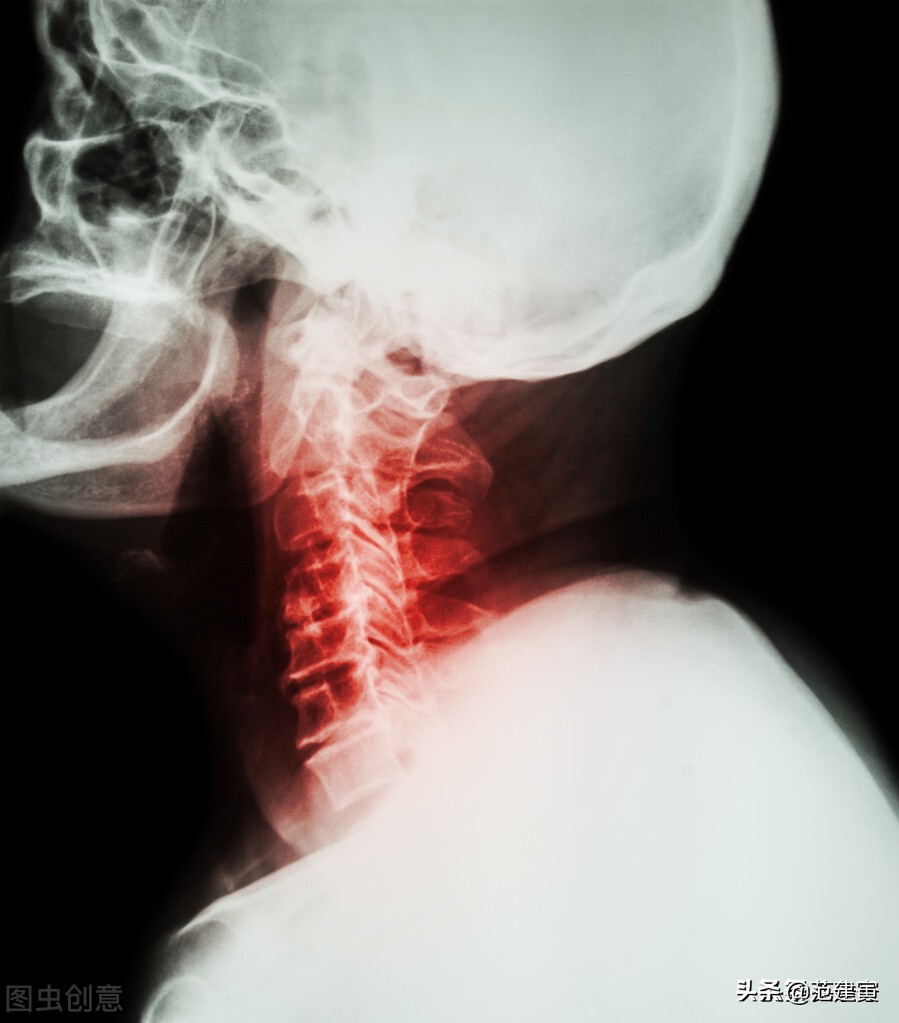

2.X线有颈椎曲度改变、不稳等表现。

3.影像学所见与临床表现一致。

2.影像学检查显示椎管狭窄、颈椎退行性改变。

3.X 线片有颈椎退行性变的异常所见。

3.X线片有失稳或颈椎退行性变的异常所见。